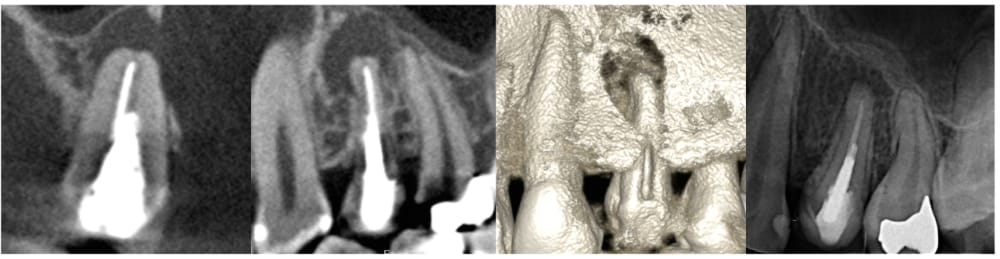

2年の経過観察

術後24ヶ月が経過時点でのCT画像では、もともとはっきりと写っていた根の先の黒い部分は完全に消失し、骨の回復が認められます。被せ物の適合にも問題なく、良好な経過をたどっています。